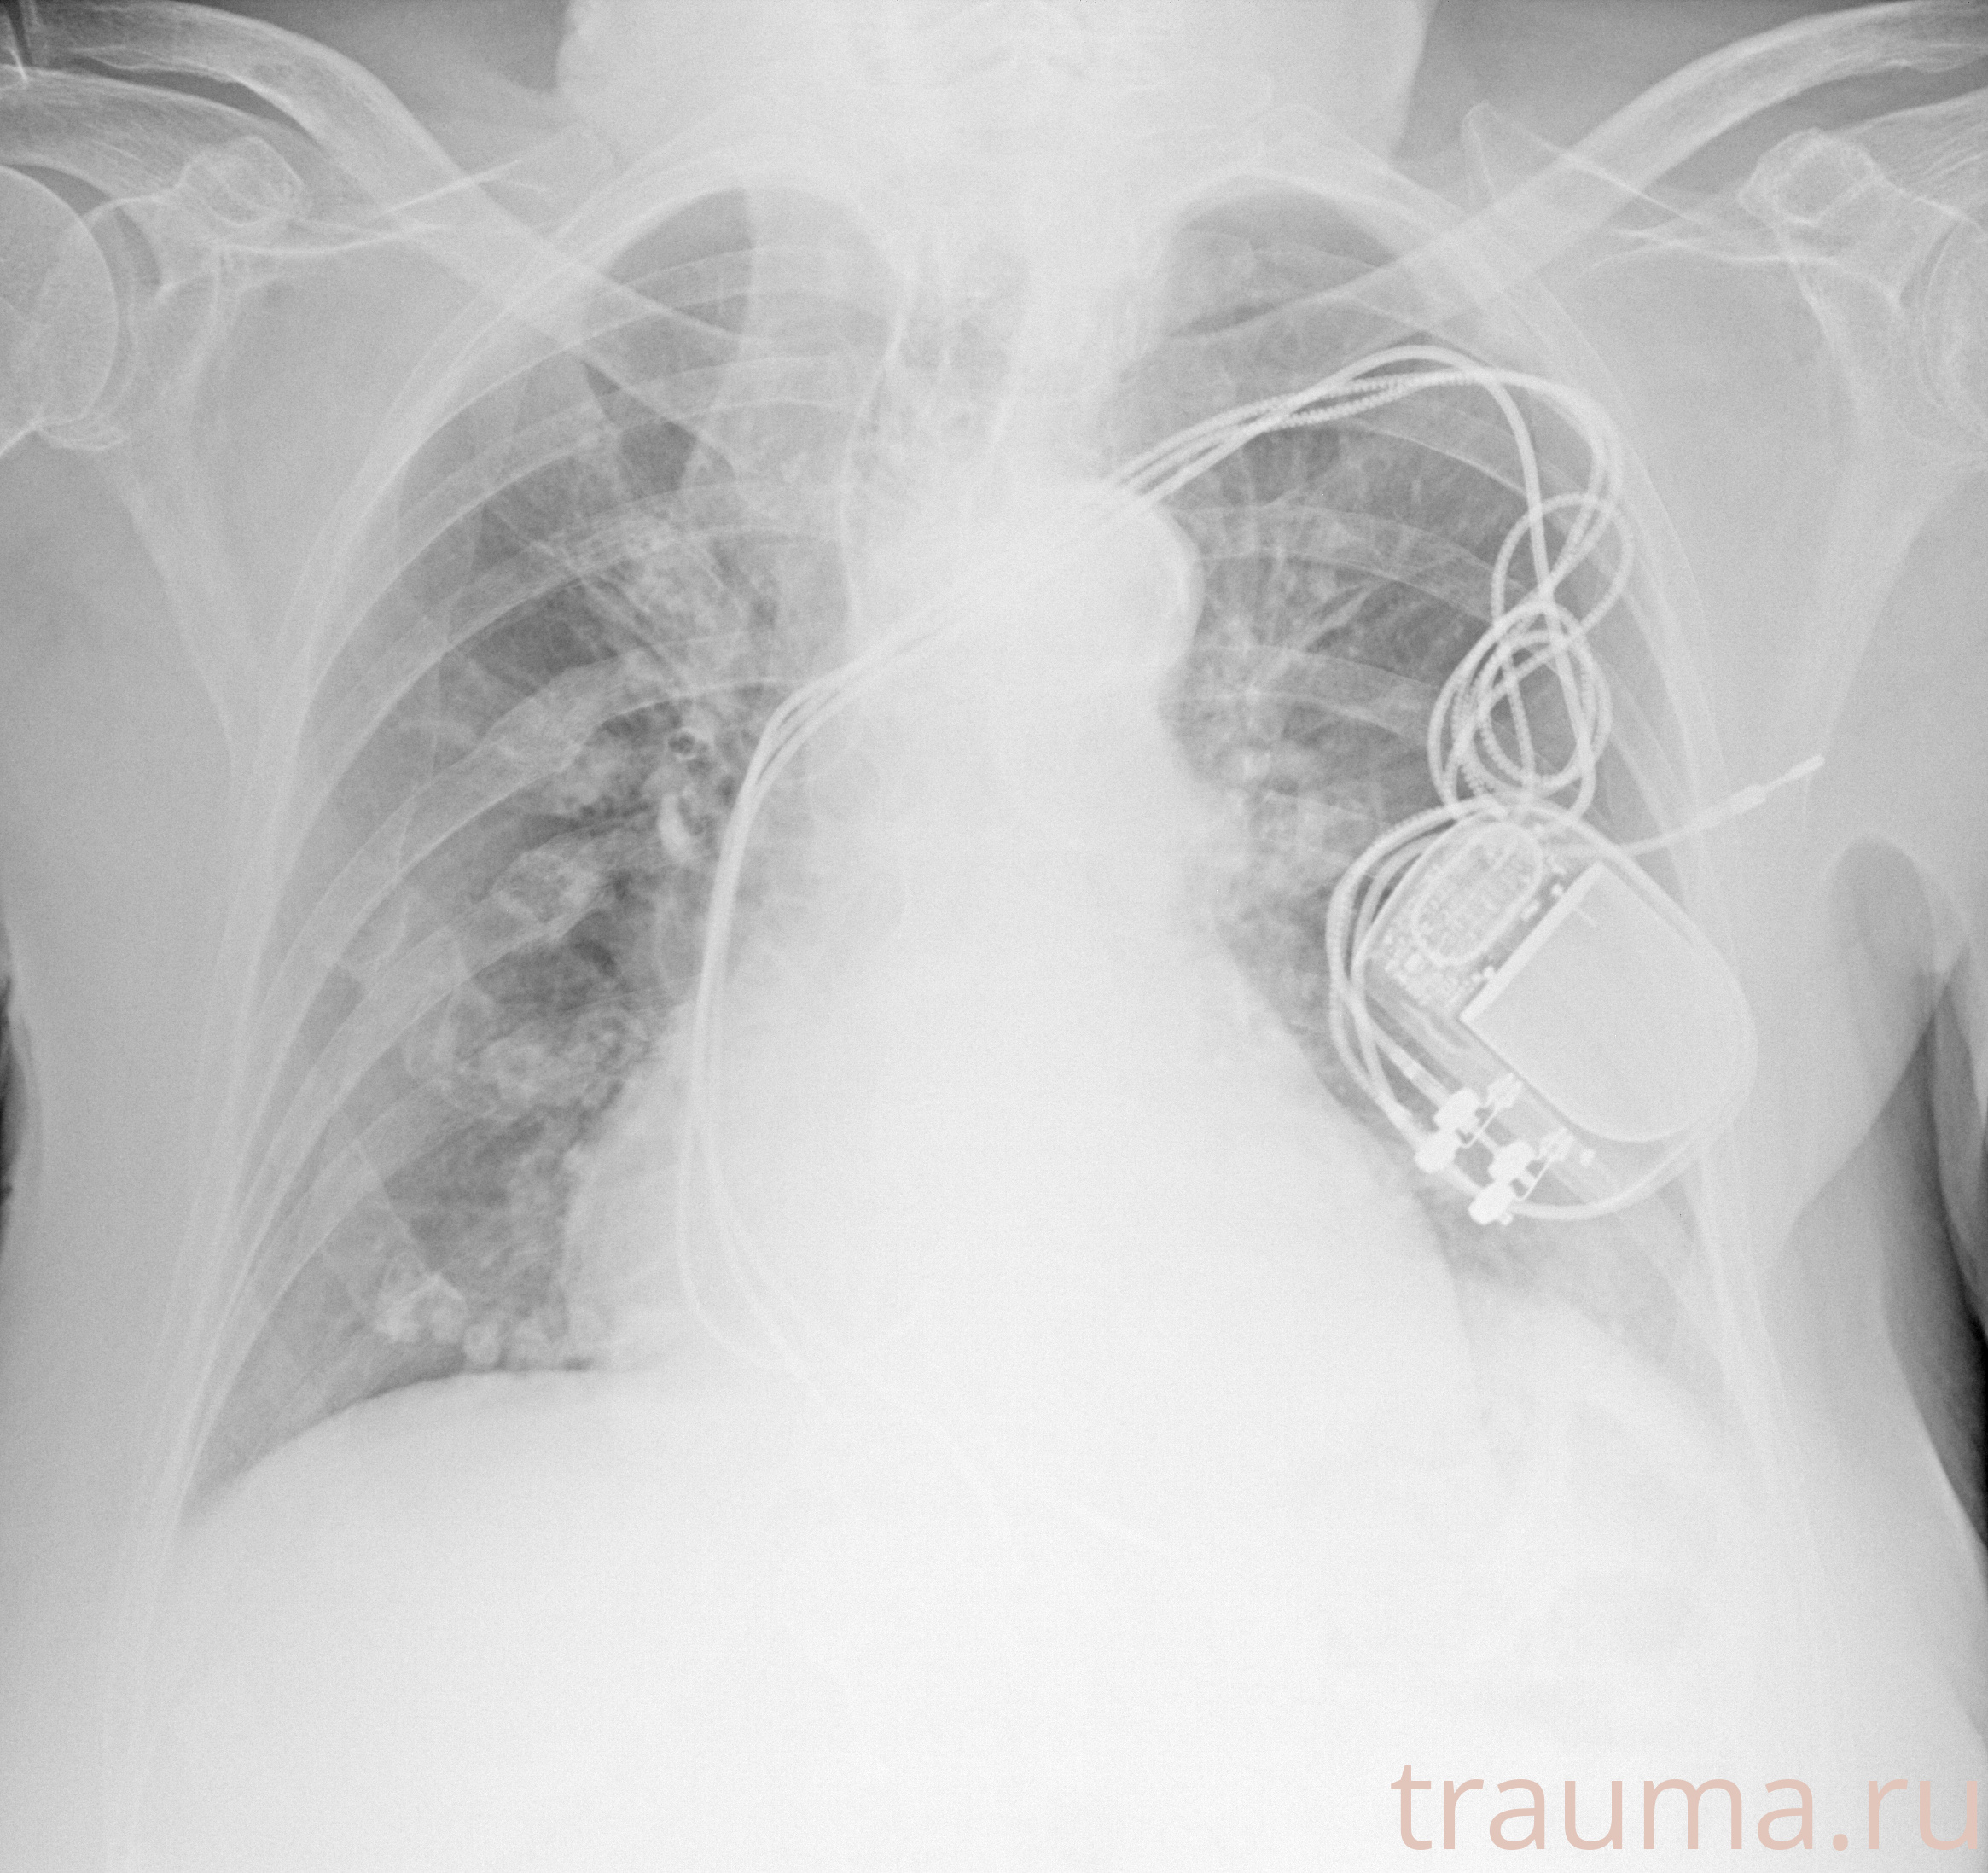

Рентгенограммы

Рентген на дому: по вашему адресу приезжает врач-рентгенолог, травматолог-ортопед с мобильным рентгеновским аппаратом, проводит диагностику травмы или заболевания, делает необходимые рентгенограммы, дает рекомендации по дальнейшему лечению. Получить качественные снимки в домашних условиях возможно благодаря уникальной методике, разработанной МосРентген Центром для института  Склифосовского

при переломе шейки бедра и пневмонии от компании МосРентген Центр - партнера Института имени Склифосовского